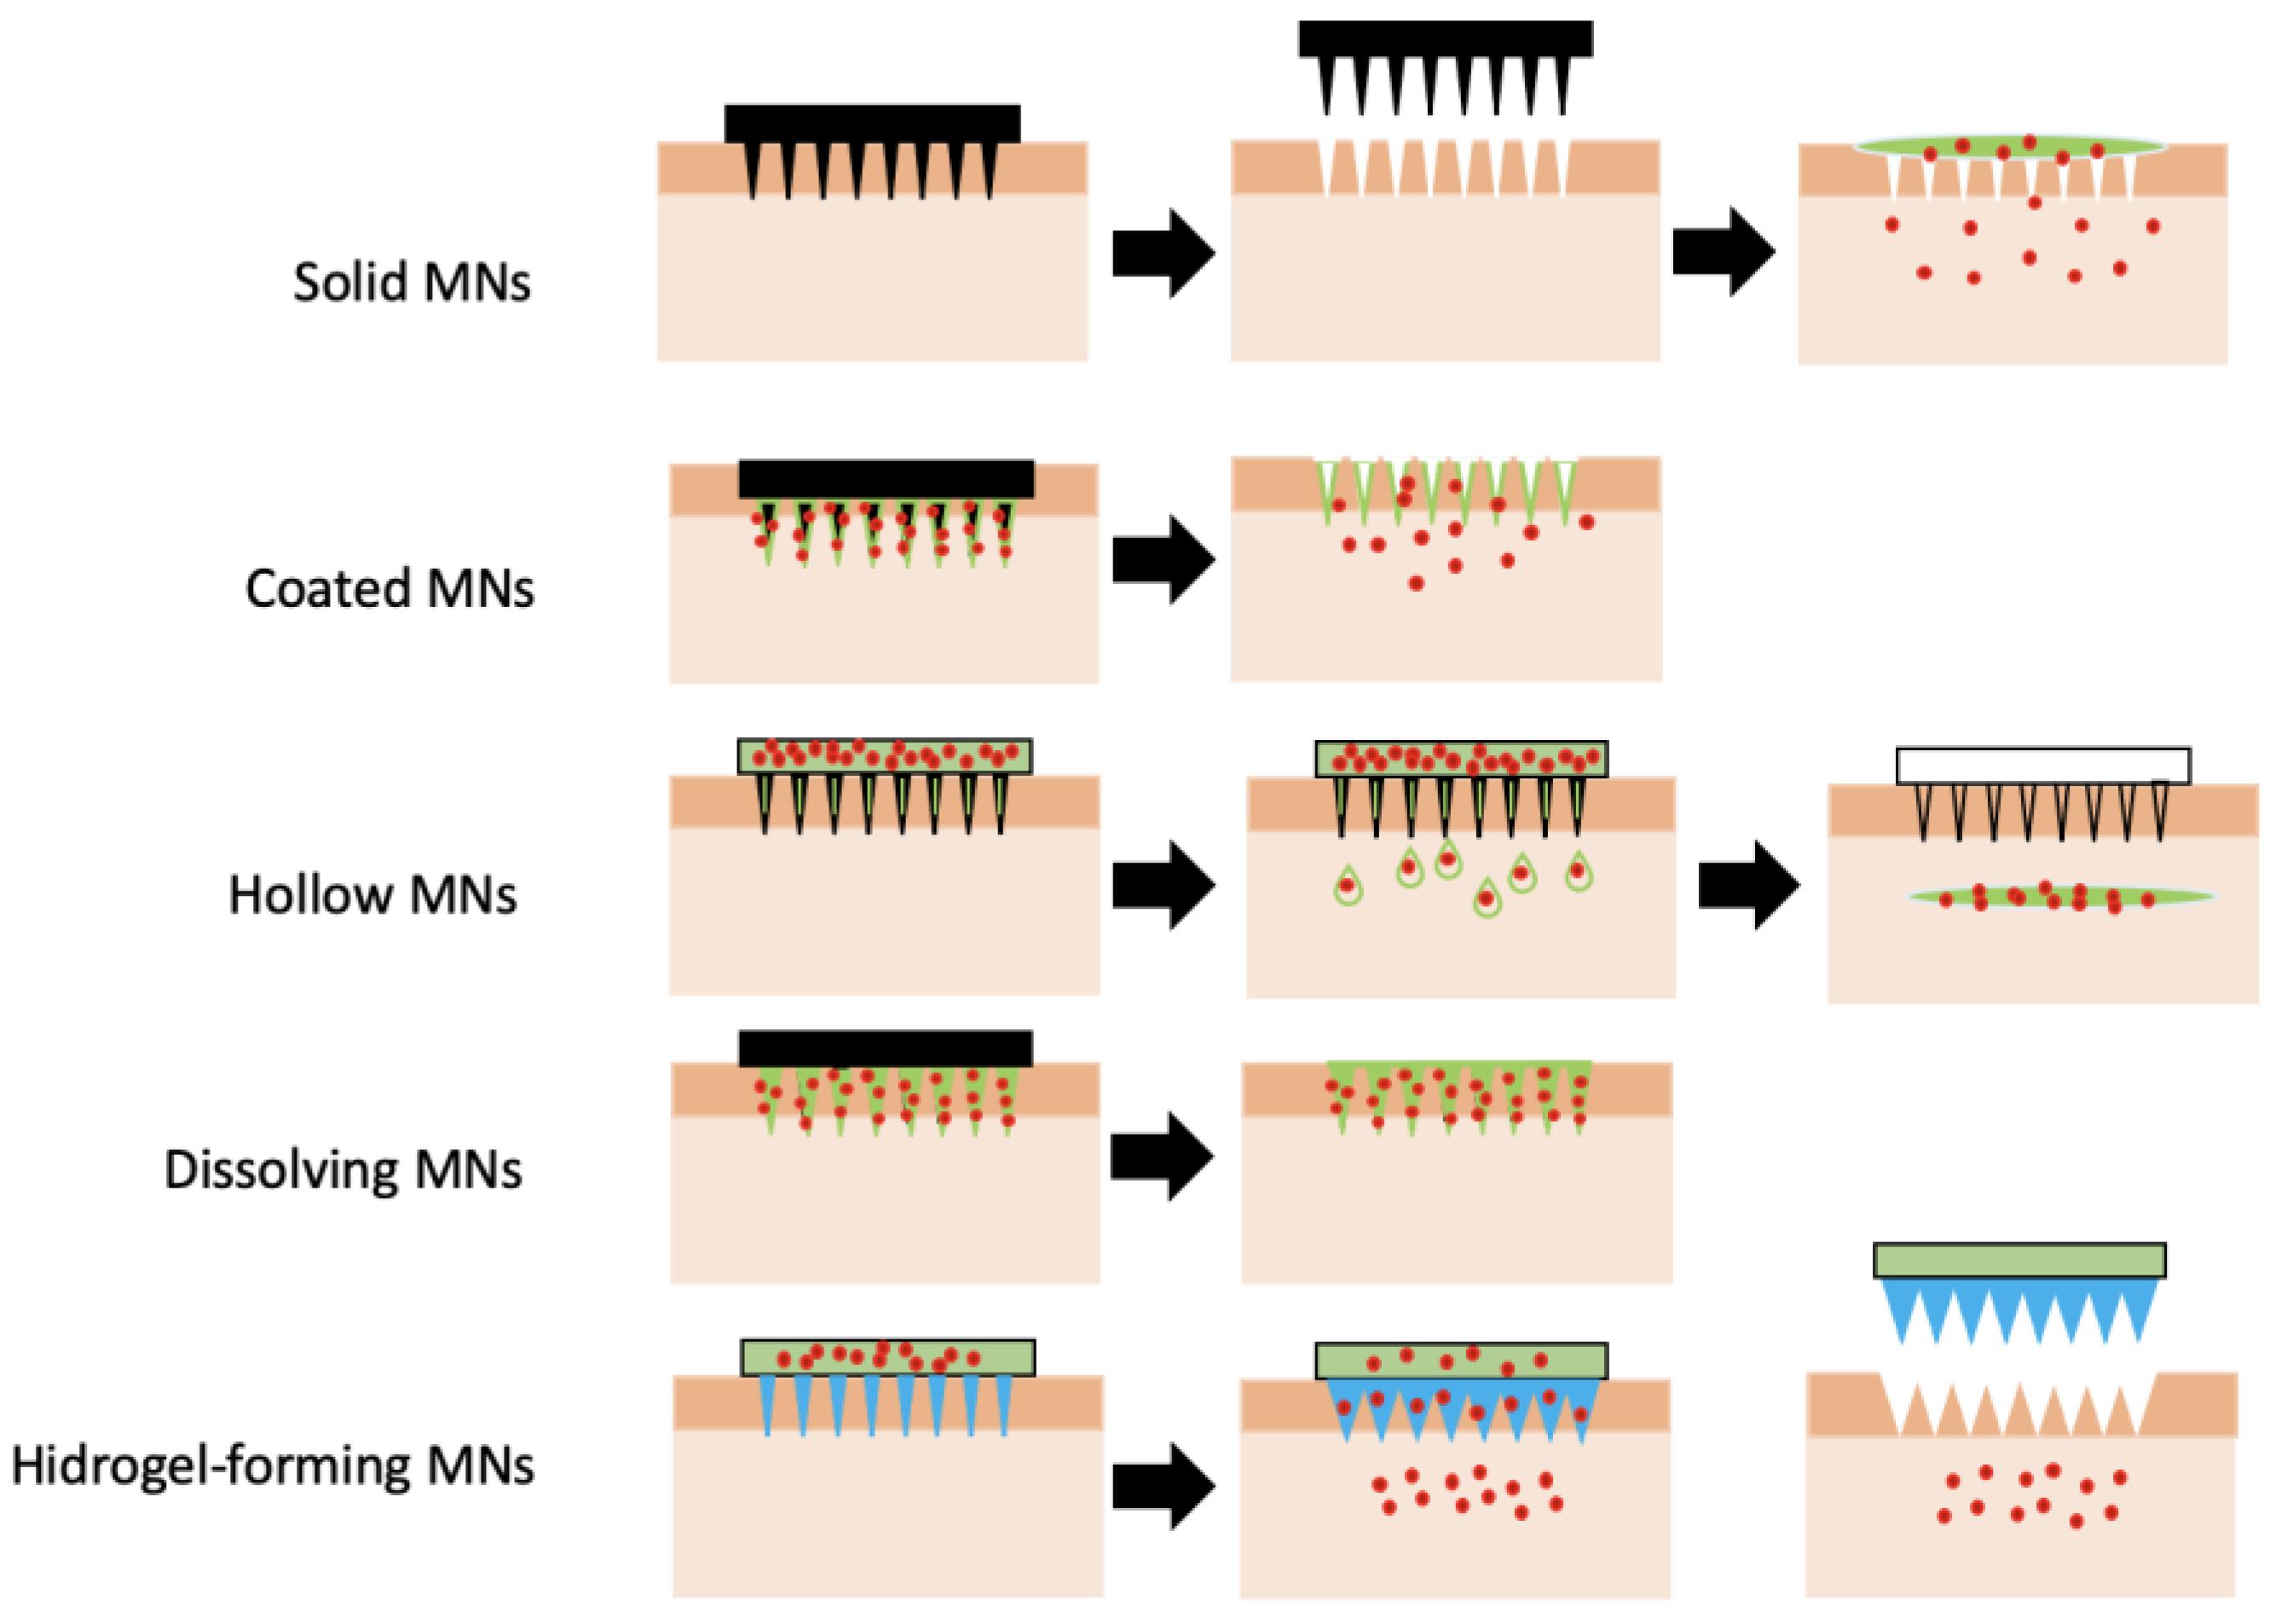

2.3.1. Types of Microneedles Concerning the Technique of Drug Loading and Delivery

2.3.2. Polymeric Microneedles